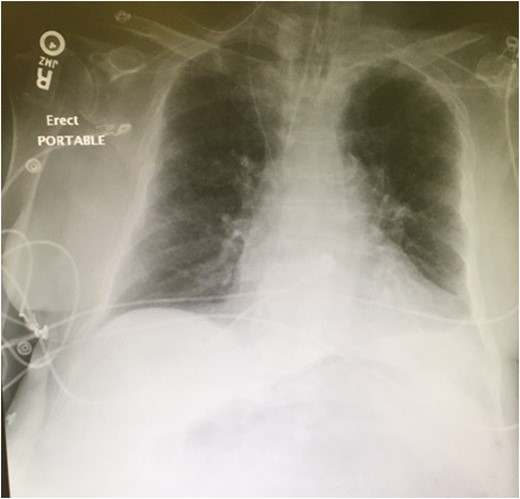

The patient subsequently became tachycardic and tachypneic. Increased work of breathing was noted with an oxygen saturation of 63%. The patient was placed on a non-rebreather mask, and his oxygen saturation subsequently increased to 99%. Shortly after the non-rebreather was placed, the patient became somnolent, responsive only to sternal rub. The patient was intubated for airway protection and plans made for transport to the SICU. Portable semi-upright chest x-ray demonstrated an endotracheal tube in proper position, no pneumothorax, and possible left pleural effusion. The tip of the NGT was not initially visualized (Fig. 3).

Portable semi-upright chest x-ray demonstrating an endotracheal tube in proper position, no pneumothorax, and possible left pleural effusion. No evidence of widened mediastinum or free air under the diaphragm. The nasogastric tube is visible coursing through the right internal jugular vein to the superior vena cava. The tip of the nasogastric tube is not visible.